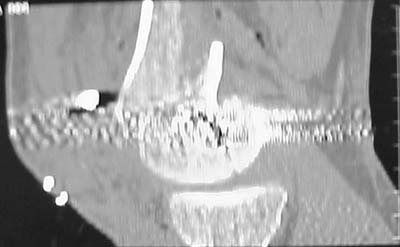

A CT and knee xrays would help identify lateral condyle comminution and/or a "hoffa fragment" of the posterior condyle. I am concerned that the lateral cortex is not sufficient to give purchase for a retrograde IMN. blocking screws could improve this as a possibility.

See attached case that was done several years ago before LISS. He had comminuted trochlea and anterior blocking screws were used to prevent anterior IMN cut-out.

Use 6.5 mm cannulated screws if you have and place one anterior to where IMN will go if anterior cortex if insufficient and AP screws on either side of the IMN out of the trochlea to provide some additional varus/valgus stability. I worry about the leg going into valgus w/ the lack of lateral cortex.